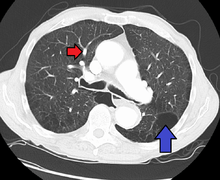

In terms of the diagnosis of pulmonary hypertension, dictates it can be of five major types, a series of tests must be performed to distinguish pulmonary arterial hypertension from venous, hypoxic, thromboembolic, or miscellaneous varieties. Further procedures are required to confirm the presence of pulmonary hypertension and exclude other possible diagnoses. These generally include pulmonary function tests; blood tests to exclude HIV, autoimmune diseases, and liver disease; electrocardiography (ECG); arterial blood gas measurements; X-rays of the chest (followed by high-resolution CT scanning if interstitial lung disease is suspected); and ventilation-perfusion or V/Q scanning to exclude chronic thromboembolic pulmonary hypertension.[27][28] Clinical improvement is often measured by a "six-minute walk test", i.e. the distance a patient can walk in six minutes. Stability and improvement in this measurement correlate with better survival.[29]

.jpg)